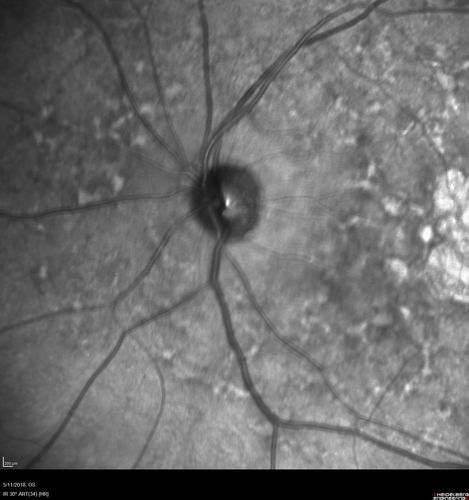

Stargardt's Macular Dystrophy

62 year old man with good vision

Stargardt's with Pisciform Flecks